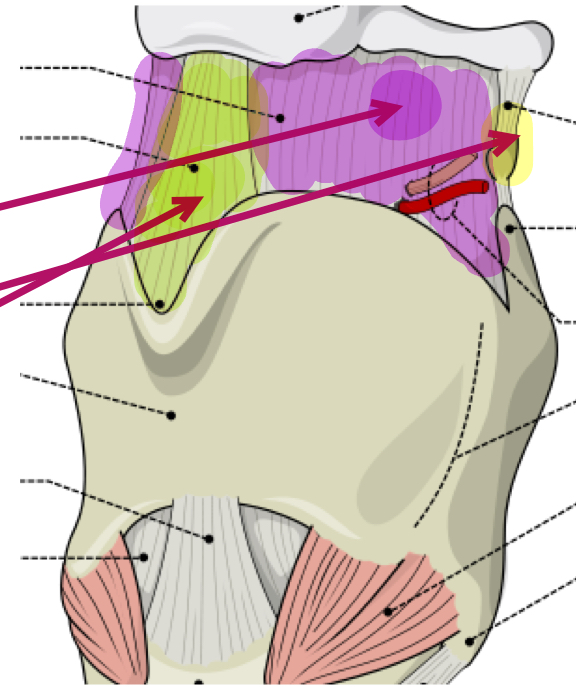

What is the purple membrane?

Thyrohyoid membrane

What is the green ligament?

Middle thyrohyoid ligament

What is the yellow ligament?

Lateral thyrohyoid ligament

What is this muscle?

Lateral cricoarytenoid (LCA) (adduct VF)

What is this muscle?

Transverse arytenoid (adduct VF)

What is this muscle?

Oblique arytenoid (pull apex medially, assist in adducting VF)

What is this muscle?

Posterior cricoarytenoid (PCA) (rocks arytenoid out, abduct VF)